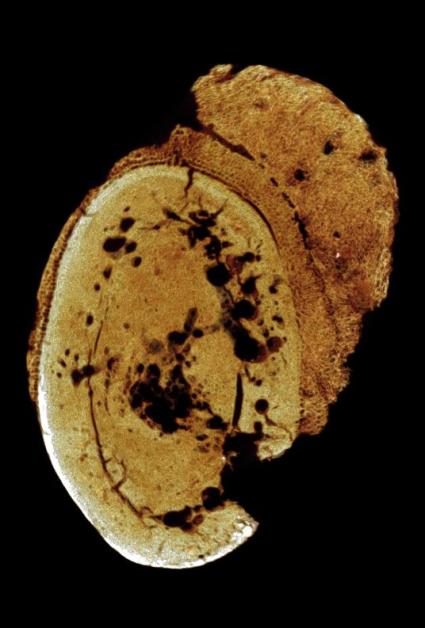

A Different Image

of the same boneUsing a method called micro-CT imaging, the research team studied detailed 2-D and 3-D images of the fossil’s interior. Images recorded the density differences within the bone and generated views of the fragment from all directions.

The abnormal growth pattern of bone tissue—including a distinctive, cauliflower-like external appearance—led the team to diagnose the condition as osteosarcoma, which today afflicts mostly children and young adults.

“We compared the images,” says Odes, referring to the fossil and a modern biopsy specimen. “It was bingo.”

The fossil, a fragment of a toe bone from the left foot, is the only part of the skeleton that was found. It preserved too little information to determine which hominin species it belonged to, whether it was an adult or a child, or even if the cancer was the ultimate cause of death.